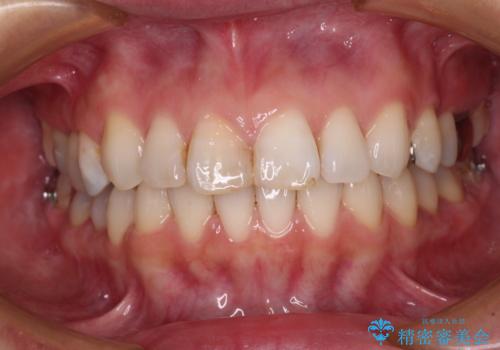

【モニター】前歯のデコボコを治したい インビザラインを用いた矯正治療

- 前歯のデコボコを治したいとのことで来院された患者様です。

上下顎ともに歯列全体の後方移動とIPR(歯と歯の間を削る)によってデコボコが解消するように設計し、インビザラインにより治療を行うこととしました。

しっかりと装着時間を守ってくださったのですが、途中妊娠にともなう悪阻や出産といったイベントがあり、予定よりも治療期間が長くなりました。